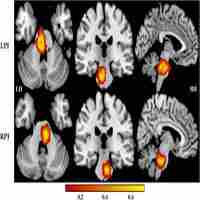

| Abstract | Introduction: This study aimed to evaluate whether engagement in leisure activities is linked to measures of brain structure, functional connectivity, and cognition in early old age.Methods: We examined data collected from 7,152 participants of the United Kingdom Biobank (UK Biobank) study. Weekly participation in six leisure activities was assessed twice and a cognitive battery and 3T MRI brain scan were administered at the second visit. Based on responses collected at two time points, individuals were split into one of four trajectory groups: (1) stable low engagement, (2) stable weekly engagement, (3) low to weekly engagement, and (4) weekly to low engagement.Results: Consistent weekly attendance at a sports club or gym was associated with connectivity of the sensorimotor functional network with the lateral visual (β = 0.12, 95%CI = [0.07, 0.18], FDR q = 2.48 × 10–3) and cerebellar (β = 0.12, 95%CI = [0.07, 0.18], FDR q = 1.23 × 10–4) networks. Visiting friends and family across the two timepoints was also associated with larger volumes of the occipital lobe (β = 0.15, 95%CI = [0.08, 0.21], FDR q = 0.03). Additionally, stable and weekly computer use was associated with global cognition (β = 0.62, 95%CI = [0.35, 0.89], FDR q = 1.16 × 10–4). No other associations were significant (FDR q > 0.05).Discussion: This study demonstrates that not all leisure activities contribute to cognitive health equally, nor is there one unifying neural signature across diverse leisure activi... |